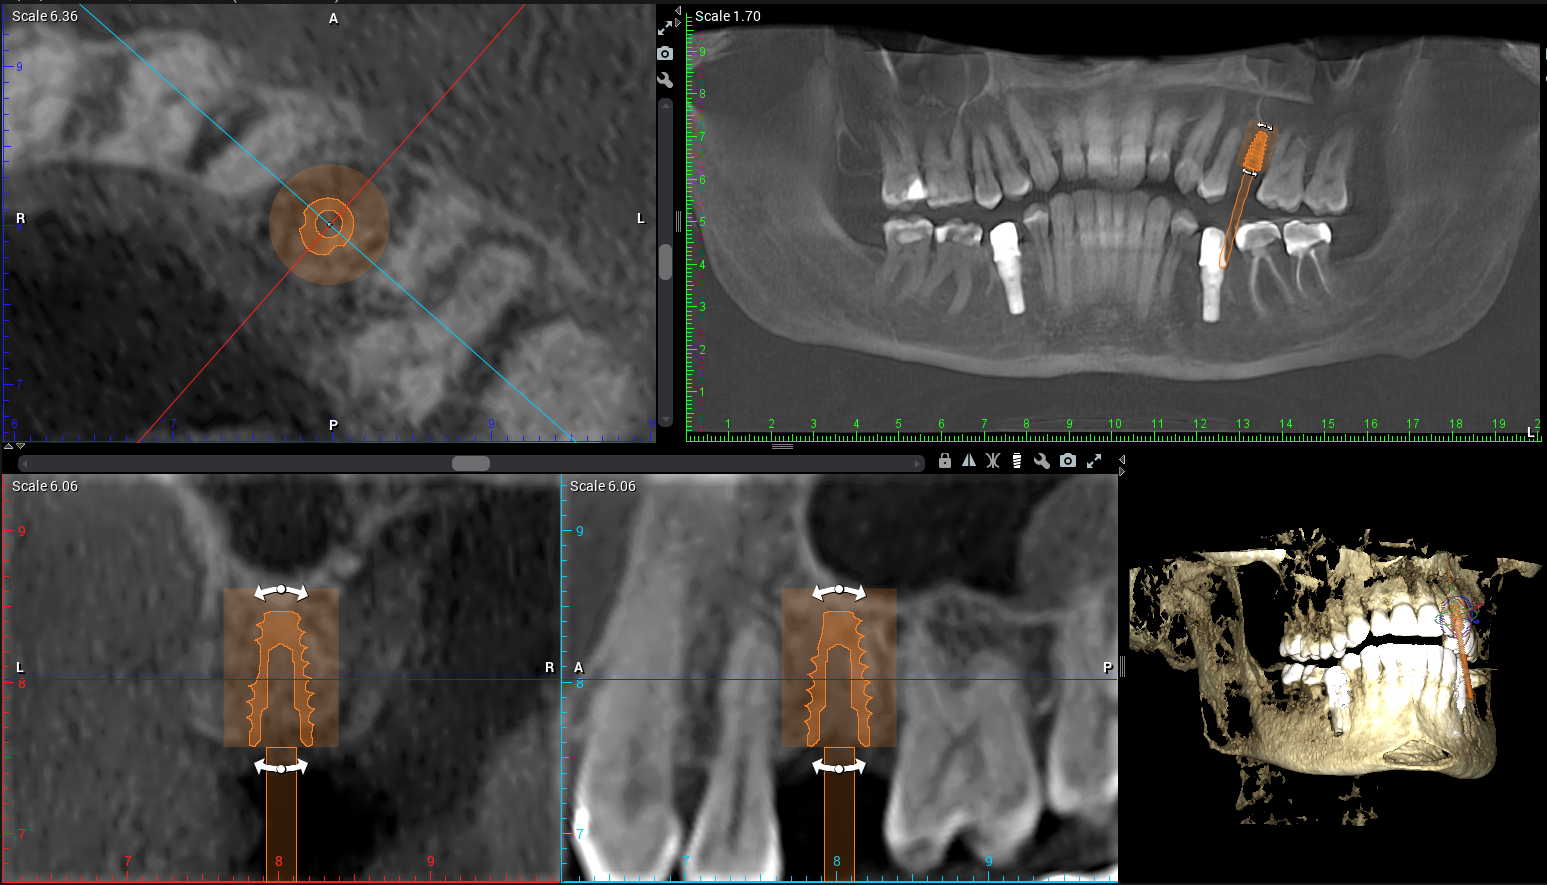

At Teuscher Legacy Dental, every implant case is planned with 3D cone beam CT imaging and digitally designed surgical guides — the same technology used by other leading surgical centers.

Visualize bone quality, and sinus anatomy, and nerve locations

Place implants with extreme precision

Often shorten healing time and improve comfort

Optimize location of future crown (the chewing part of the implant)

(Source: Vercruyssen et al., Clin Oral Implants Res 2014;25:94–99)

This first step also helps make sure the patient is on the same page with what to expect a final result to look like. We also go over financial details and timeline. This way the patient knows what to expect every step of the way!CBCT 3D Planning

Before taking any teeth out or diving into implant placement, we start with a CBCT scan to evaluate the bone structure in 3D. This shows us the height, width, and quality of bone, and how close we are to adjacent roots or anatomical structures. Planning the exact implant location here prevents complications later.Site Preparation & Grafting (if needed)

CBCT (3‑D imaging) is used to assess bone quantity and quality and check for any sinus or nerve issues. There should be an evaluation of overall health (e.g., diabetes, smoking, medications) and other risk factors. Gum health should also be assessed (are there active gum infections?) and whether bone grafting is needed.Use of guided surgical planning

CBCT imaging allows us to measure bone density, identify vital structures (like nerves and sinuses), and plan the exact position of your future implant.

Using digital treatment planning, we design a custom surgical guide to ensure the implant is placed with millimeter accuracy.

Example of Teuscher Legacy Dental’s 3D implant Planning Software

3D scans (CBCT imaging) and digital planning lead to better fit, healing, and long-term success. A 2D X-Ray is less expensive, but also doesn’t allow for the same precision in planning where the implant post will sit in your jawbone. Sometimes, a dentist will use the 3D scan to generate a surgical guide, which allows for even greater precision when surgically placing the post.